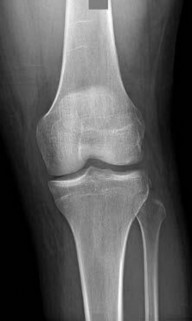

Question 8:

A 13-year-old overweight boy presents with a 3-week history of right groin and knee pain. He walks with a limp. On examination, when his right hip is flexed, it obligatorily externally rotates. Radiographs show a slip of the proximal femoral epiphysis. Which radiographic line is used to diagnose this condition?

Correct Answer: Klein's line

Explanation:

The clinical scenario describes Slipped Capital Femoral Epiphysis (SCFE). Klein's line is drawn along the superior edge of the femoral neck on an AP pelvic radiograph. In a normal hip, this line should intersect a portion of the lateral capital femoral epiphysis. In SCFE, the line passes superior to the epiphysis or intersects less of it compared to the contralateral normal side (Trethowan's sign).